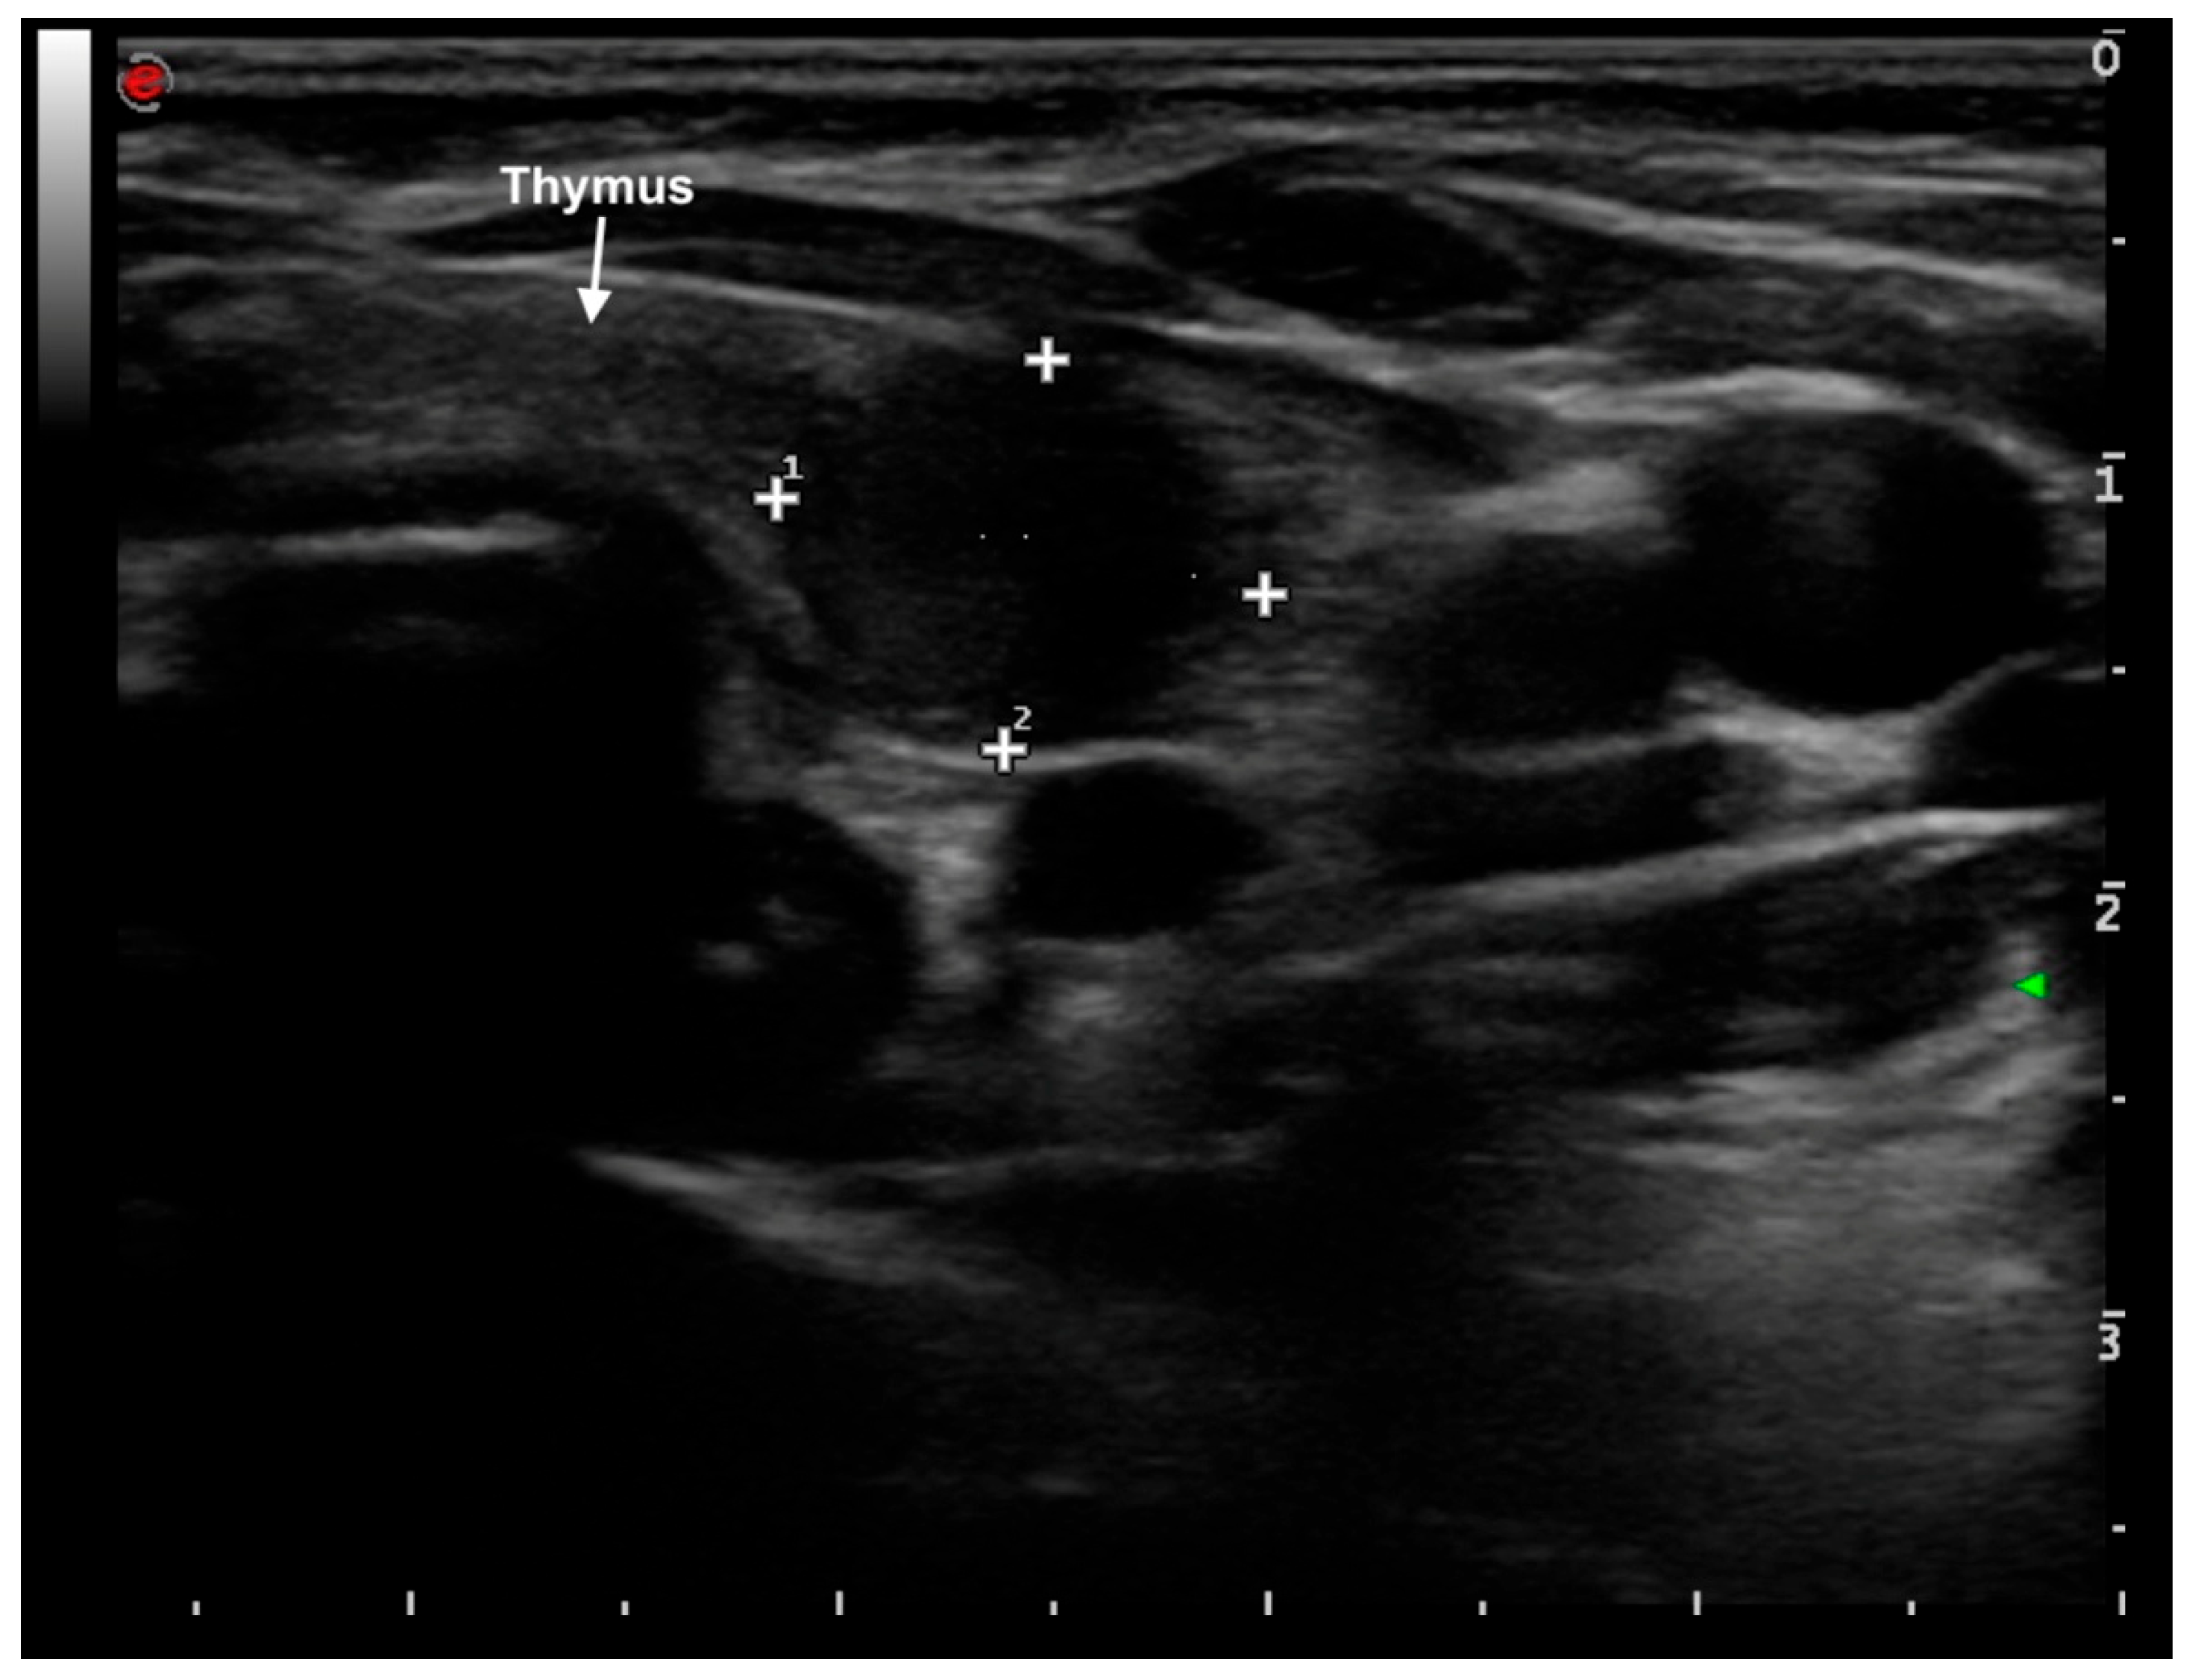

2. Case Presentation